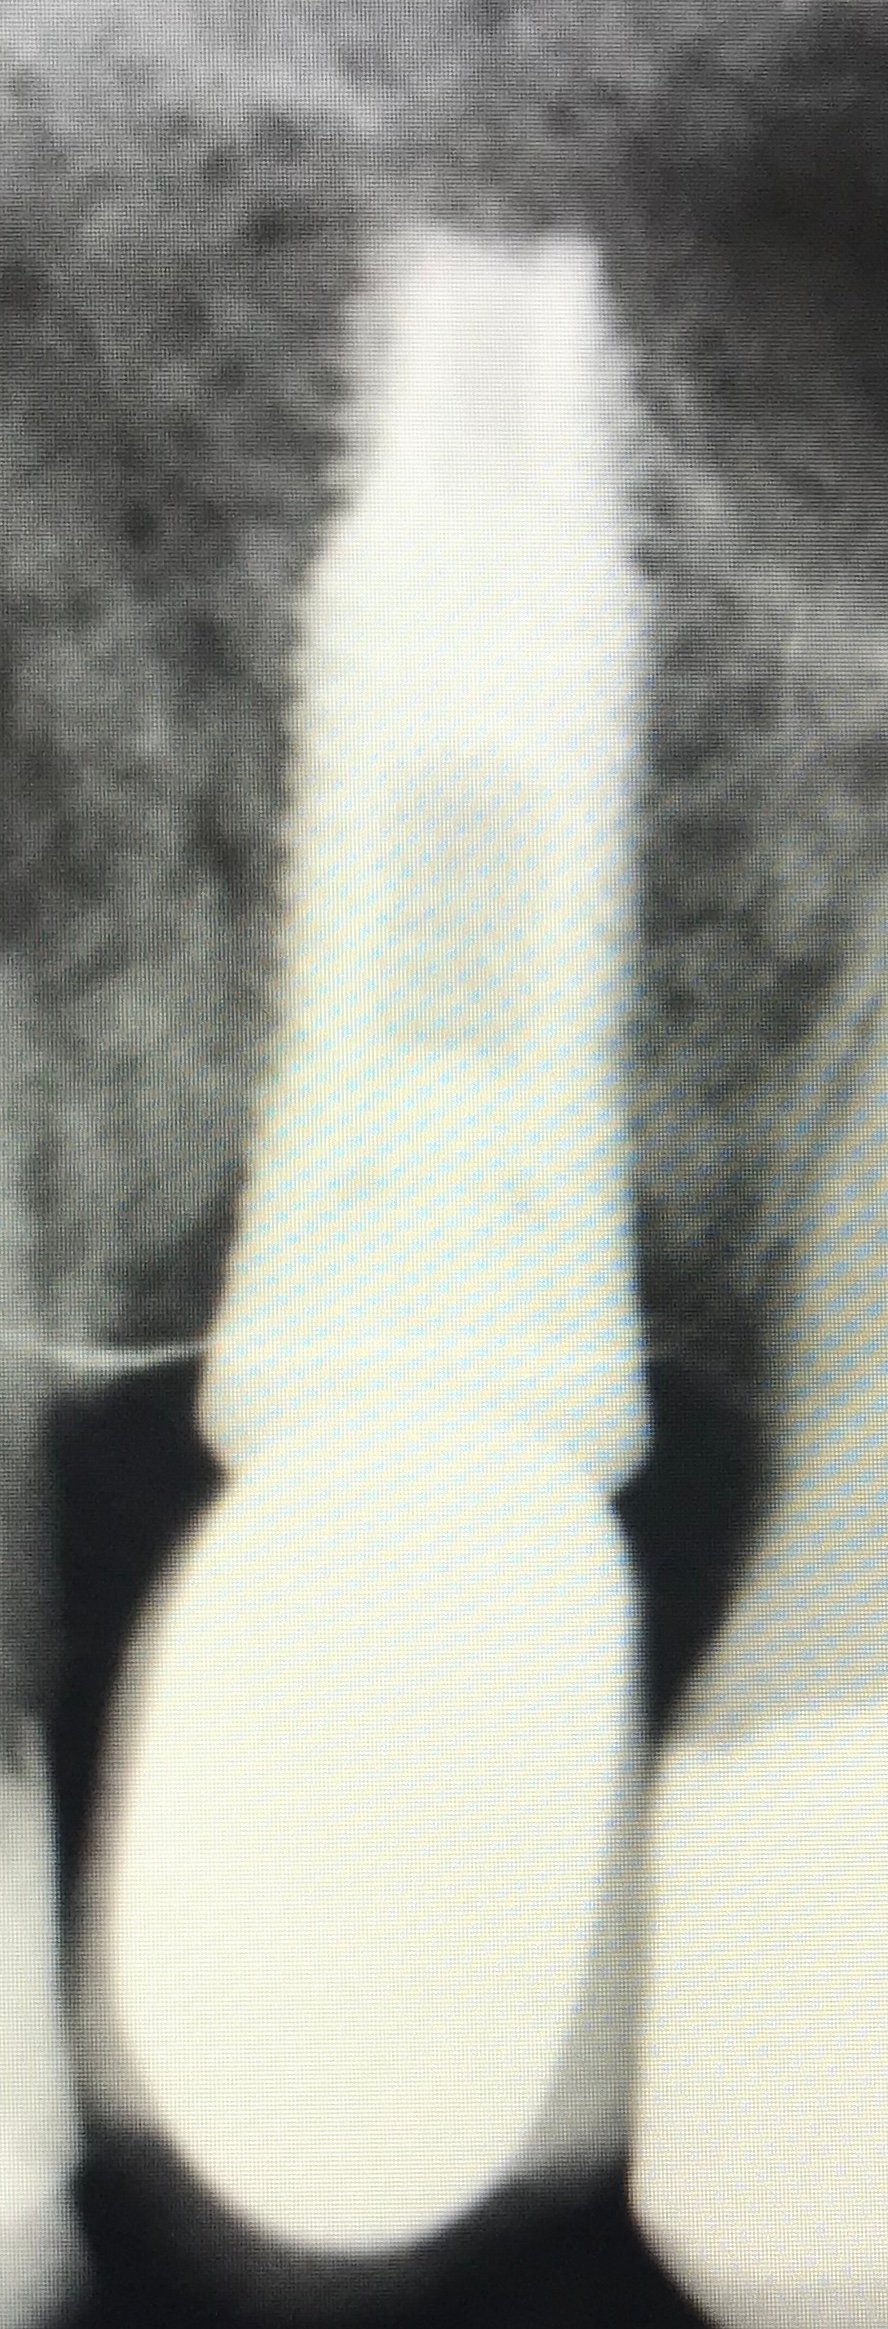

Implante 25 desconocido. Me han confirmado de las propias casas comerciales ASTRA y AVINENT que no es un implante de los suyos. Si resultase difícil la identificación, probaré a perforar [...]